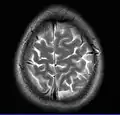

Cross-sectional T1-weighted MRI of a healthy human brain acquired with an ultra high-field MR of 7 Tesla field strength

This axial T2-weighted (CSF white) MR scan shows a normal brain at the level of the lateral ventricles.